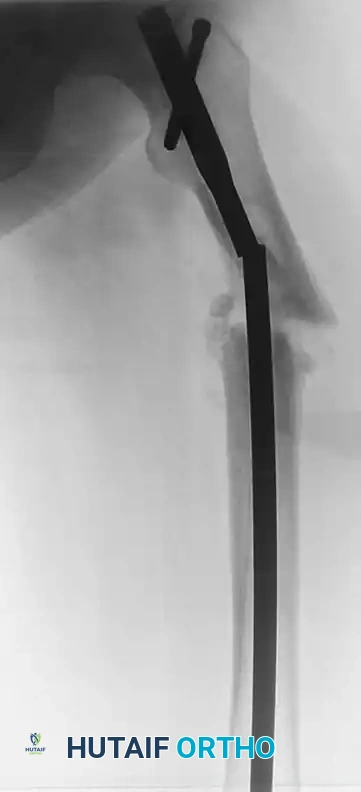

Intramedullary Nail Breakage

Intramedullary nails are load-sharing devices. When a diaphyseal fracture fails to heal, the nail is subjected to massive bending moments, particularly in the subtrochanteric region of the femur or the proximal third of the tibia. Nail breakage typically occurs directly at the level of the nonunion.

FIGURE 53-49 A: Broken femoral intramedullary nail resulted in nonunion that required bone grafting and plate fixation. The failure occurred at the zone of maximum bending stress, necessitating a comprehensive revision strategy.

If possible, it is best to augment the fracture prior to catastrophic failure if delayed union is identified early. However, once the nail breaks, extraction of the retained distal segment becomes a significant technical challenge.